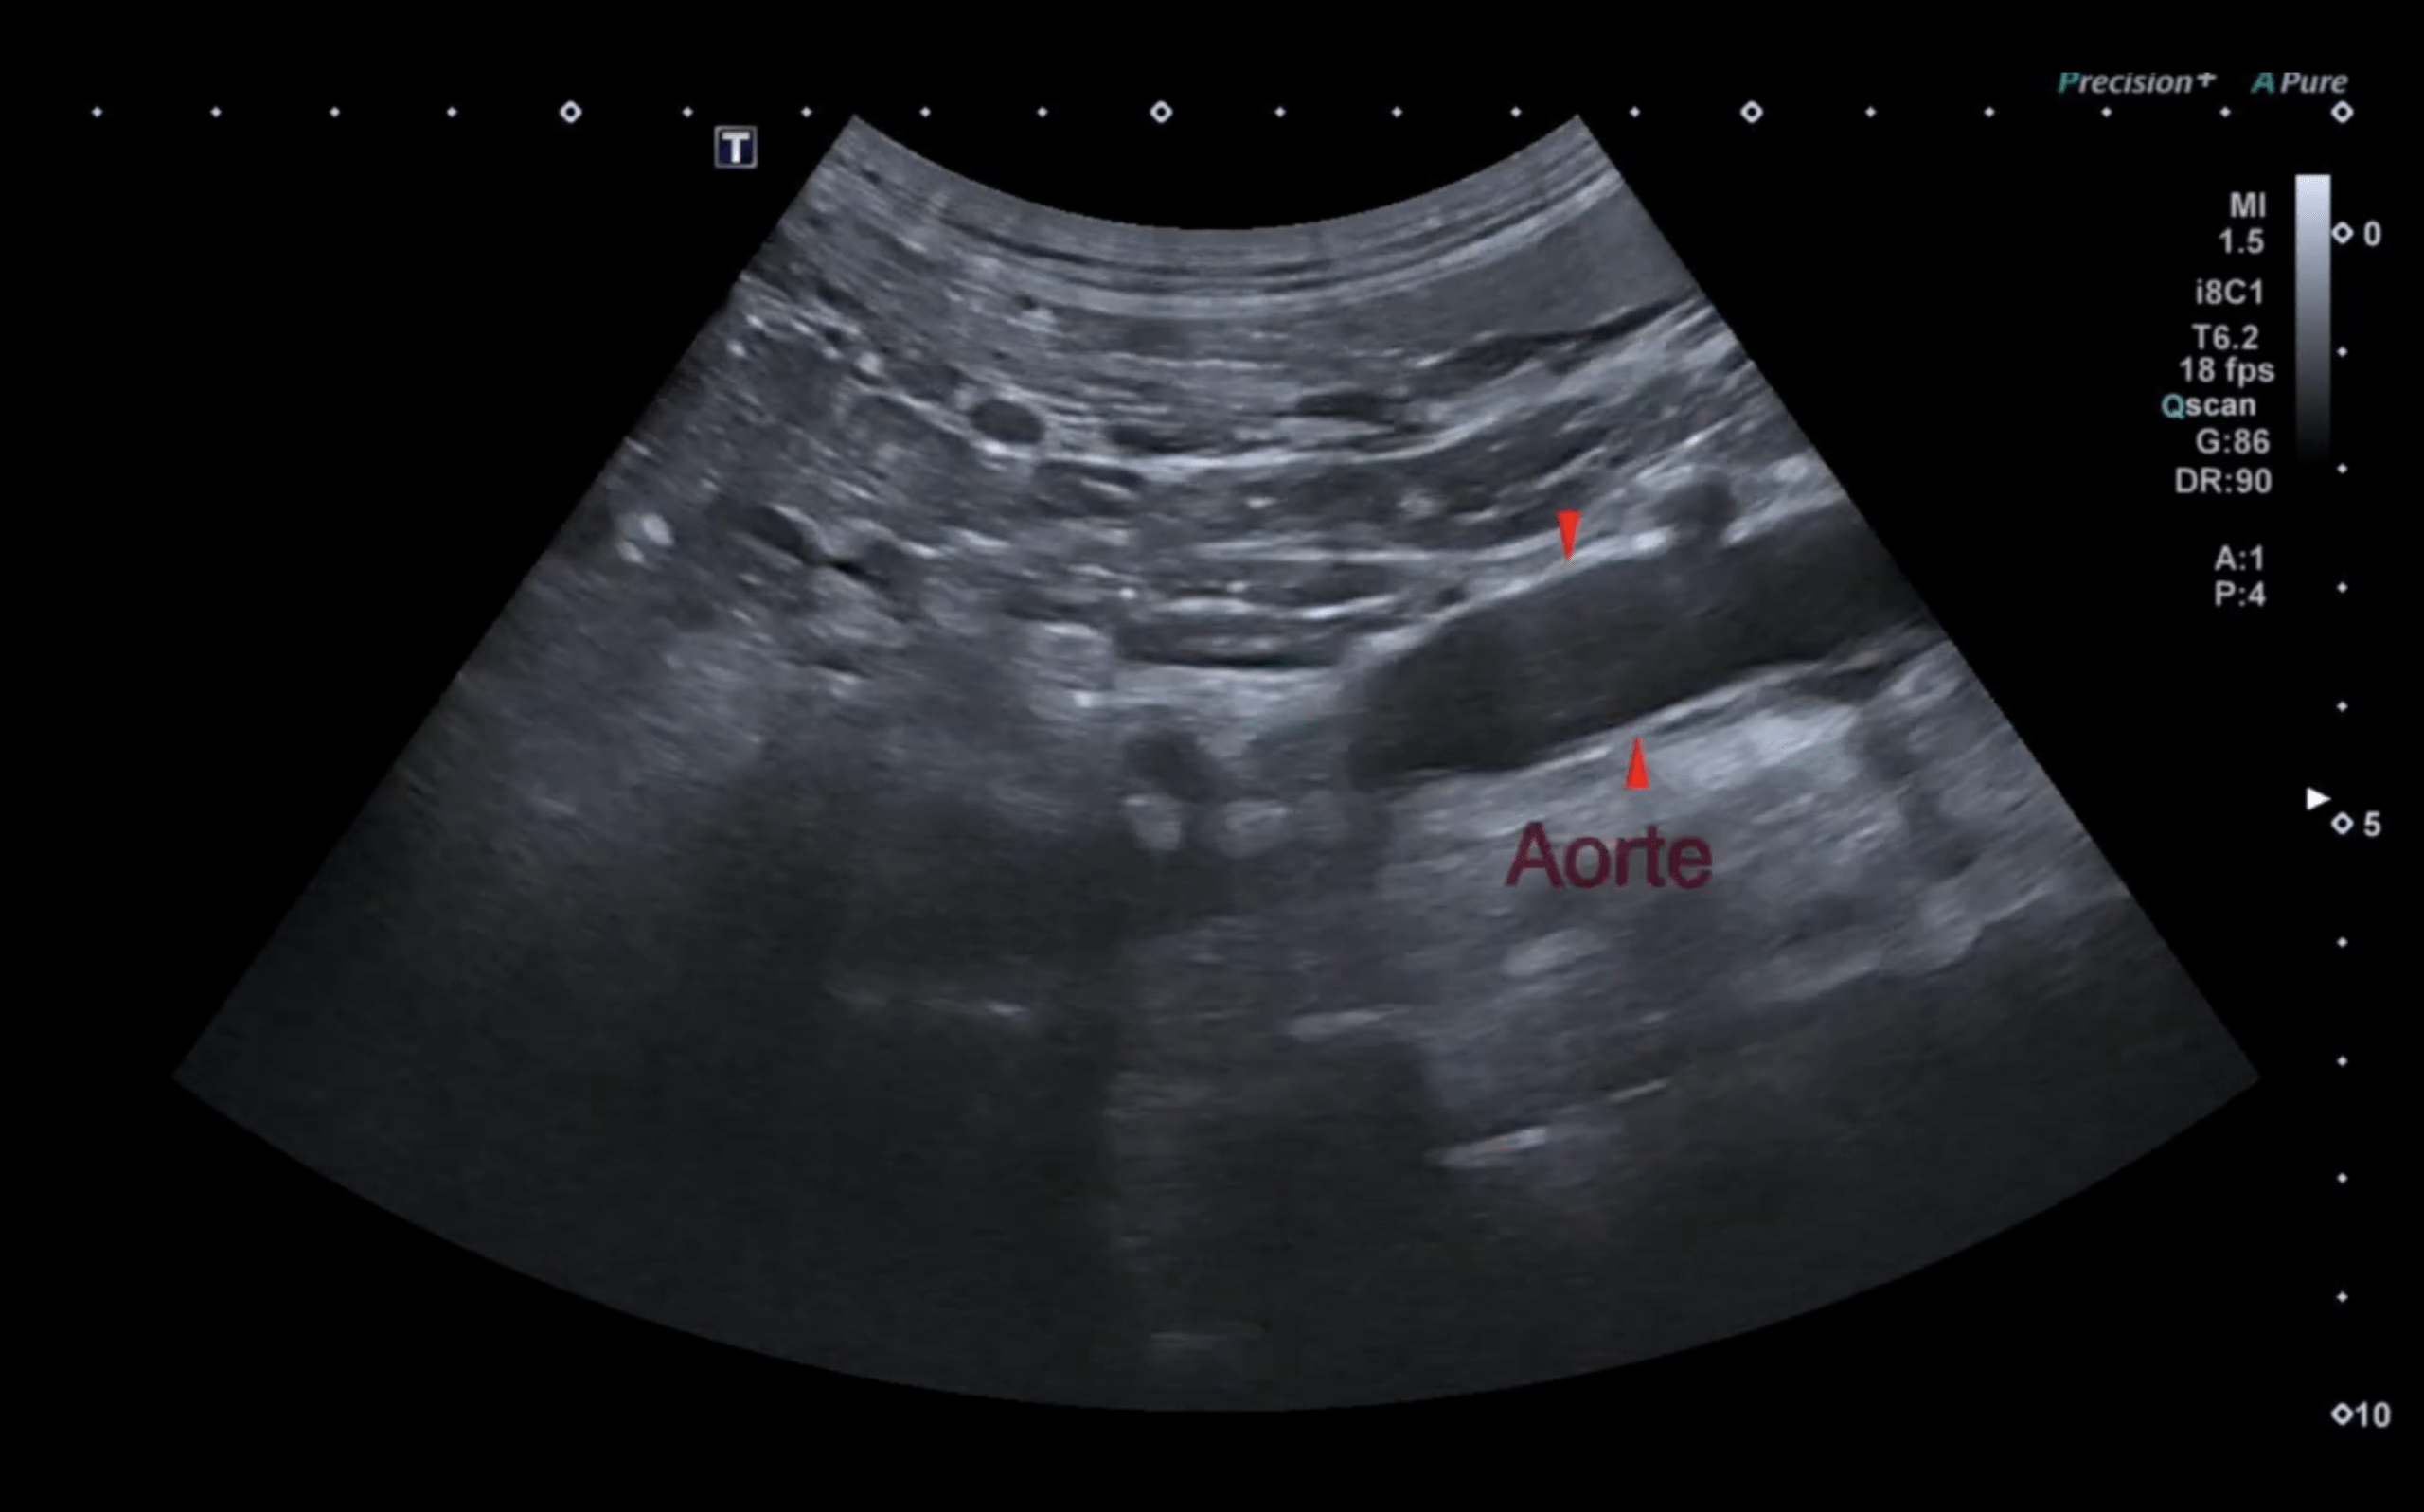

Identifier les glandes surrénales à l’échographie

Le Dr Florian Azoulay vous explique comment trouver les glandes surrénales à l’échographie. Lire la suite